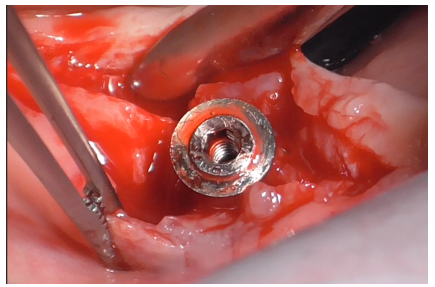

The Ultrasonic Device was equipped with the ES004E insert (patented by Esacrom, Dr. Tarquini), creating an ultrasonic bath (Figure 23).

Figure 23

Initially, this insert was used with physiological saline flow (Figure 24) for approximately 1 minute. Subsequently, Ambramicin was applied to the site (Figure 25), capsules were specially opened to use the powdered antibiotic inside, activated for 1 minute using the same bell-shaped insert with physiological saline flow (Figure 26).

Figure 24